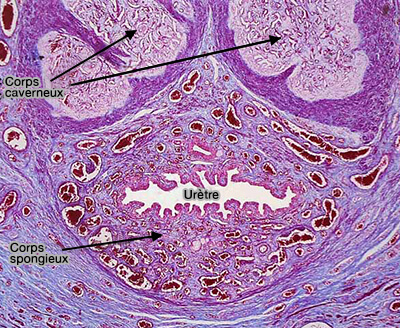

Coupe transversale du pénis du chien

(Photo : vetopsy.fr d'après Friskies)

La structure du corps caverneux est sensiblement identique à celle du corps spongieux.

1. Les trabécules entourent les aréoles ou cavernes du corps caverneux très extensibles, réseau de capillaires extrêmement dilatés, provenant de l'artère du pénis (artère pénienne), qui jouent un grand rôle dans l'érection.

Histologie des corps caverneux

(Photo : vetopsy.fr d'après siumed.edu)